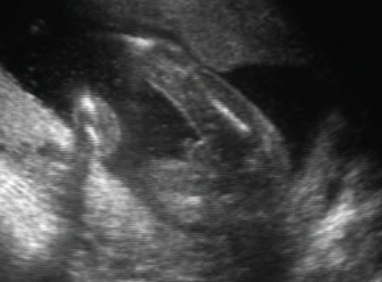

szégyenlős... :oops: ahogy forogtunk, úgy fordult ő is...

fenekét sürün láttuk, meg az összeszorított lábakat. Nevetett a dokicsaj is,azt mondta ilyen nincs :D :shock:

egészséges.Megvan mindene,jól fejlődik.De h fiú-e v lányzó nem tudni. doki szerint ha fiú lenne már tudnánk :lol: lányok szoktak igy bujdokolni :wink:

képek:

Kép

egész végig ezt az oldalát mutatta...

Kép :oops: :roll: